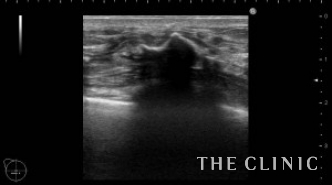

右)このカプセルをバスケットカニューレを使い、石灰化を崩しておきます。被膜がやわらかくなり折れ曲がって見えます。左)上段左側のしこりを穿刺処置したあとです。